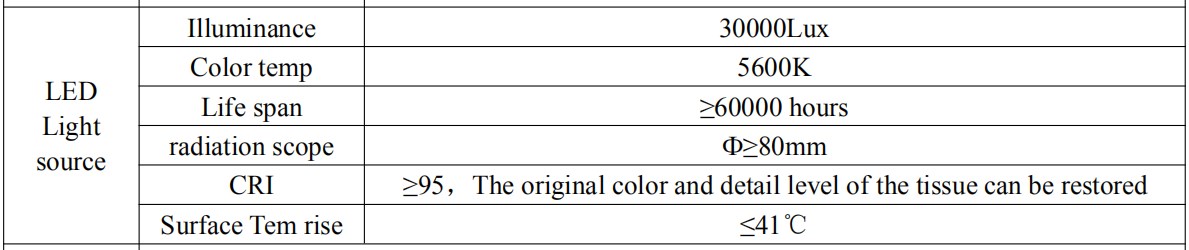

Light source technical parameter